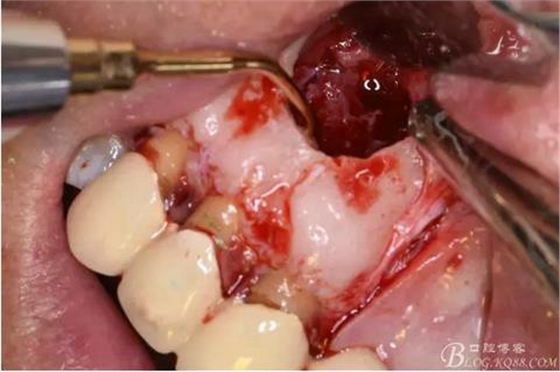

圖9.去除唇側(cè)薄的骨壁,暴露出囊壁

圖10.剝離囊壁

圖11.摘除囊壁后形成的骨腔